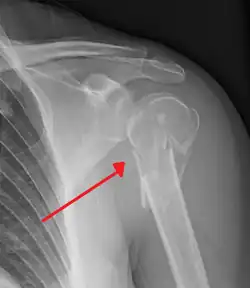

Multi-fragmented fracture of the proximal humerus with involvement of the greater tuberosity

The standard x-ray views of the shoulder include a true anterior-posterior view, a lateral (Y or outlet) view, and an axillary view.[13] A Velpeau view can be done as an alternative to the axillary view if an examinee is unable to position the shoulder for an appropriate image. This can be obtained by having the examinee lean backward 45 degrees while an xray beam is aiming towards the floor.[11]

A CT scan of the injured shoulder can be done to help further characterize the fracture and determine articular involvement. CT scan is also an option if an axillary view is unattainable.[11]